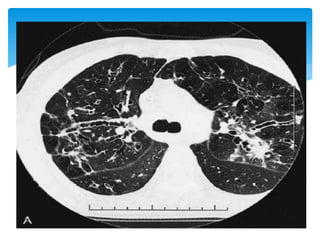

TBC MILIAR

 Múltiples imágenes

nodulares que de 1 a 2mm de

diámetro, distribuidas al

azar. Dx con Bx pulmonar

abierta.